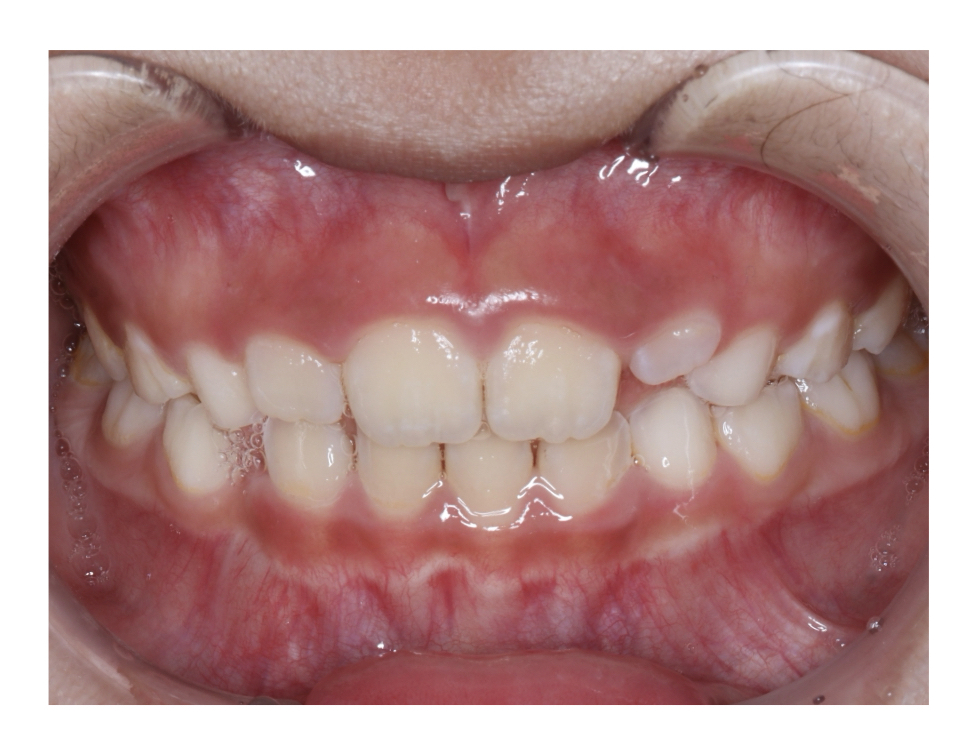

Case3

Before

After